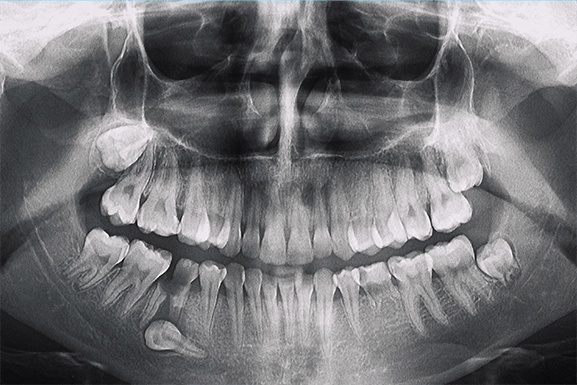

Wisdom tooth removal is a fairly common procedure. If the dentist

thinks that you need to have your wisdom tooth removed, he will

first have to confirm it through an X-ray of your mouth. This gives

him a clearer view of how your teeth are positioned.